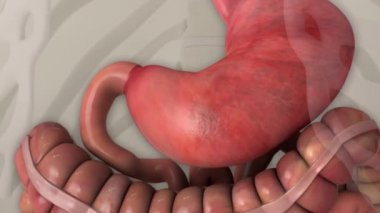

Sindirim Sistemi

MaviresimlemeİnsanKadınSağlıkkanİlaçAğızSolunumerkekkalpgövdeMidebiyolojiBilimSistemözetorgİskeletanatomiKas gücübeyinSistemlersindirimGerginakciğerlerkaraciğerBöbrekiskeletOrganlaranatomikBağırsaklarBağırsakKolondolaşımdalakBenzer İçerikler